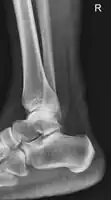

![]() | |

| Achilles tendon (a commonly affected tendon) | |